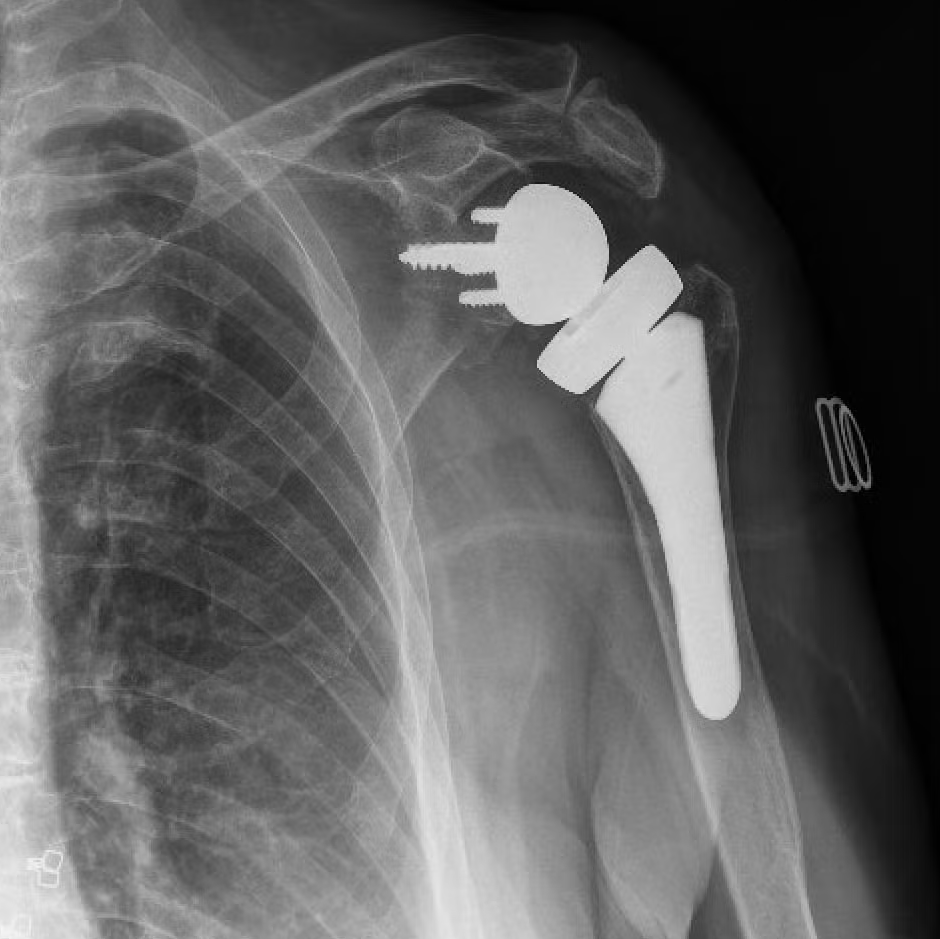

Tipos de prótesis de hombro

Prótesis anatómica

Prótesis reversa

Consiste en retirar las partes dañadas del húmero y la glenoides y reemplazarlas con implantes médicos. Existen distintos tipos de prótesis, cuya elección depende del estado del hueso, el cartílago y los tendones.